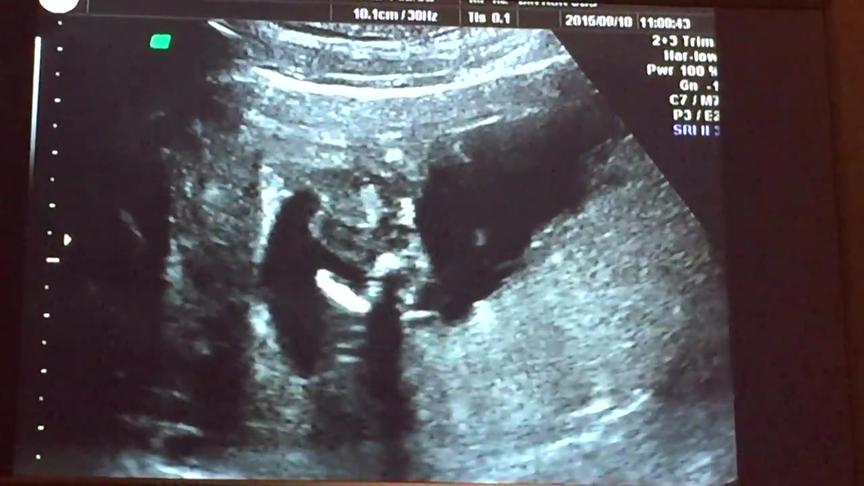

性別が分かるのは大体5ヵ月目以降と言われていますが、早いと 妊娠11週目頃 からエコー写真に写る「ベビーナブ」で 性別が判明 することも! そもそも、ベビーナブとは? 1 分鐘 11週大的寶寶 傾聽心跳。 小寶寶的心臟其實已跳動了幾週,只是之前聲音太小,未能夠聽見。 胎兒的心跳是媽媽心跳速度的兩倍,大約每分鐘1至140下。 過去一個月,寶寶的心臟已長出四個心室,然而某些分隔心室的肌肉須等寶寶出生後才會發育完成。 長出皮膚。 過去數週,胎兒身體表面已長出一層細嫩皮膚,而一層特化皮膚則開始發育成指甲及趾甲。 量妊娠11週目 お医者さんに聞いてみましょう 血液型検査や不規則抗体を調べるのはいつ頃?パパの血液検査も必要? 妊娠11週目のエコー(超音波検診)で赤ちゃんの性別がわかるの?

懷孕第11週 (11周) 分類: 懷孕第三個月(9~12週) divide 懷孕11週症狀 頭暈目眩、疲勞和頭腦混亂的癥狀有所減輕,但仍持續噁心和孕吐。 懷孕11週胎兒大小 寶寶的身高增長一倍,身長已經達到46厘米,體重達到14克左右。 divide 妳已經孕11周了 這是胎寶寶生長的關鍵一周,他的身高增長一倍,寶寶的成長速度在本周越發驚人,小家夥已經完全成型了 只要滿 13 週,寶寶生殖器官就會發育完成。故在此時照超音波時,只要寶寶角度配合正確,就可以明顯看出胎兒性別。若有進行羊膜穿刺的準媽咪,亦可藉由此檢測了解寶寶性別。通常產檢醫師會在 16 週時告知性別,並於 週產檢再次確認胎兒性別。 妊娠12週目エコーで性別やダウン症が判明?つわりが軽くなる時期 胎児の大きさの平均 妊娠12週目(妊娠4ヶ月目の1週)の赤ちゃんの大きさの平均は 60~70ミリで、体重は15~グラム程度 ですが、赤ちゃんらしい姿に進化している時期です。